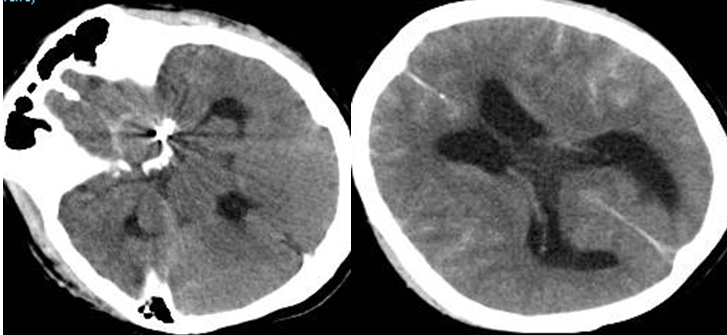

头颅CT检查提示:蛛网膜下腔出血、两肺炎症。

我院急诊的CT及DSA考虑:左侧颈内动脉床突段血泡样动脉瘤。

急查头颅CT提示:再出血,脑积水加重。